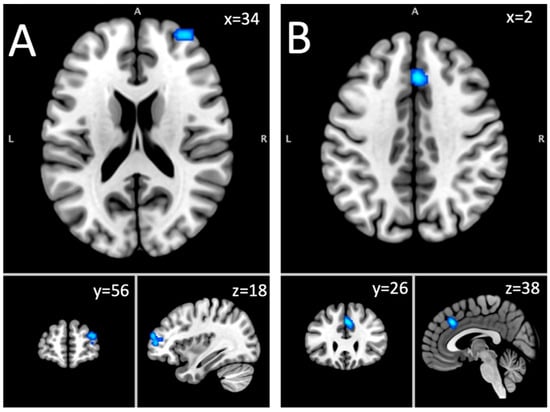

| Hyper–hypoactivation combined: short-term abstinent sample | |||||

| Putamen | L | 1096 | 0.0236 | 4.88 | −20, 12, −2 |

| Hypoactivation: short-term abstinent sample | |||||

| Middle frontal gyrus, superior frontal gyrus, sub-gyral | R | 856 | 0.016 | 4.48 | 24, 8, 66 |